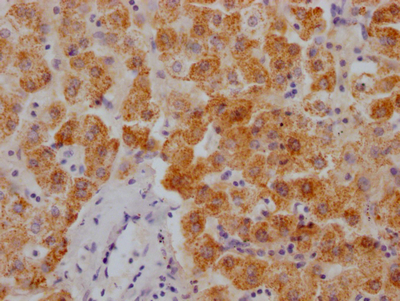

應用范圍:ELISA, IHC

Application Recommended Dilution IHC 1:20-1:200 -